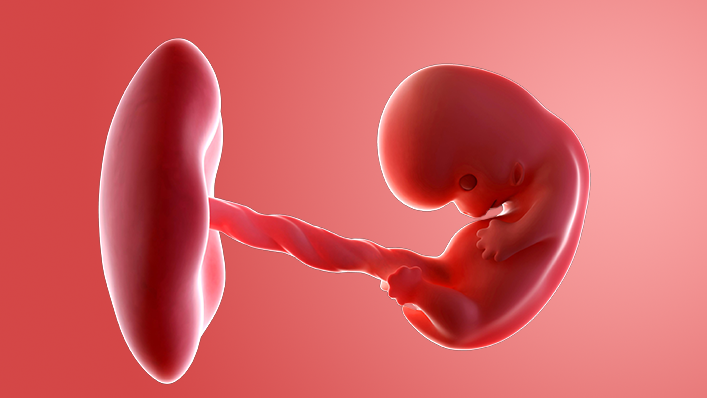

What does my baby look like?

Your baby, or embryo, is around 6mm long, which is about the size and shape of a pea. Some people think it resembles a tadpole with its little tail.

The arms and legs are starting to form and are known as limb buds. There are tiny dents where the ears will be.

There's a bump where the heart is and another bulge where the head will be. Sometimes the heartbeat can be picked up by a vaginal ultrasound scan, but you are unlikely to be offered one unless you've had IVF.

The embryo is covered with a thin layer of transparent skin.